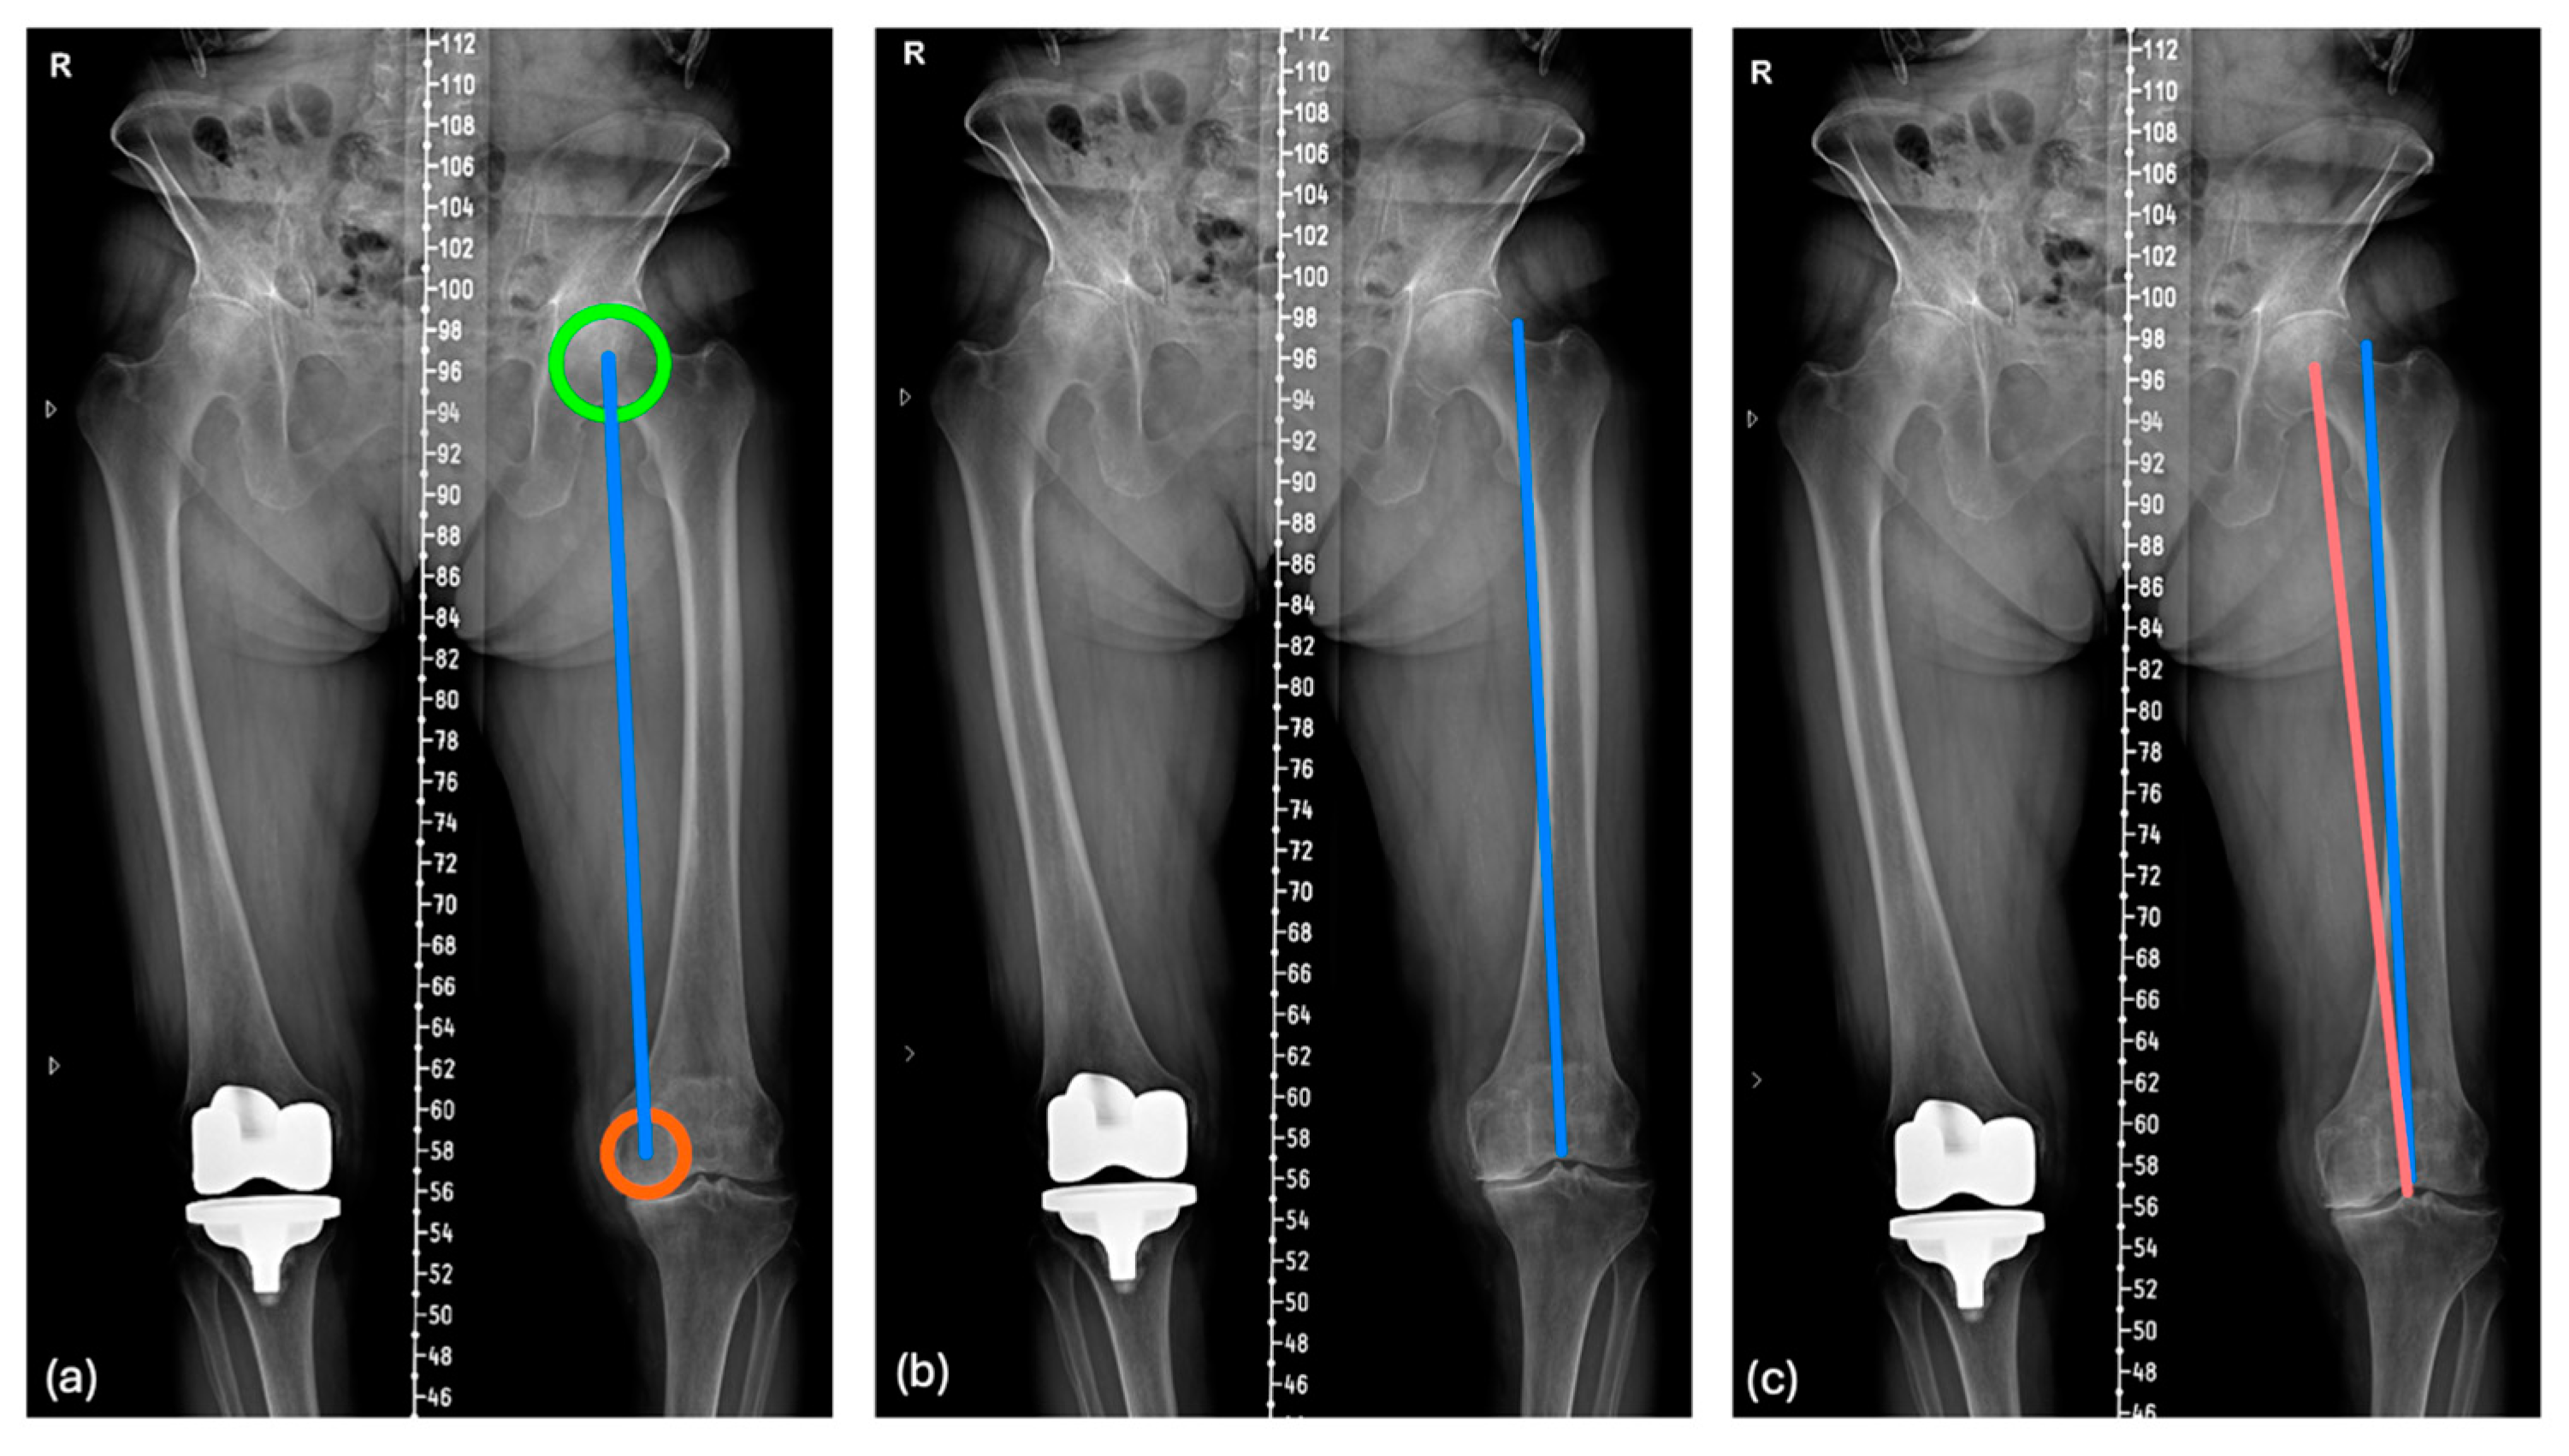

2.2. Preoperative Radiographic Measurement

2.3. Mathematical Formula for the Prediction of Postoperative PTA Orientation